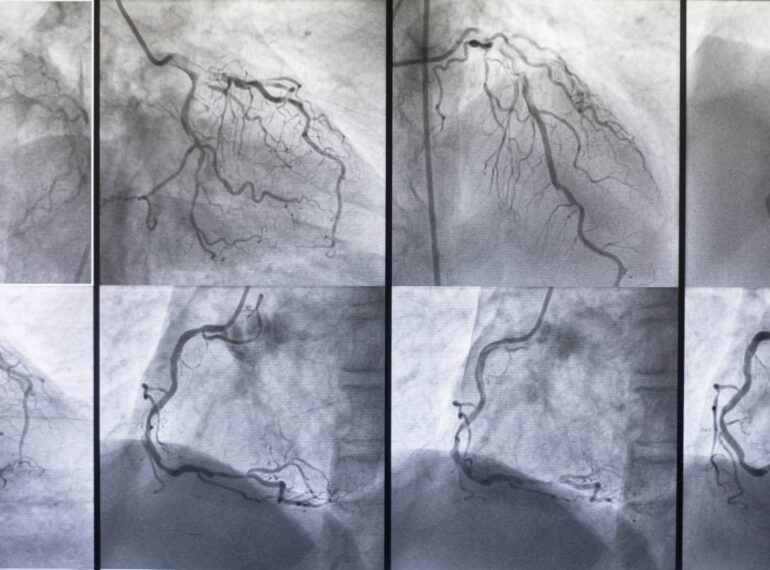

From primary angioplasty to complex stenting, receive expert treatment using the latest transradial techniques.

Coronary Angiography

Complex PCI

Dr. Honey Sharma provides advanced hospital-based cardiac care using the latest techniques and technologies. From angioplasties to device implantations, each procedure is handled with precision and compassion by a super-specialized expert in interventional cardiology.